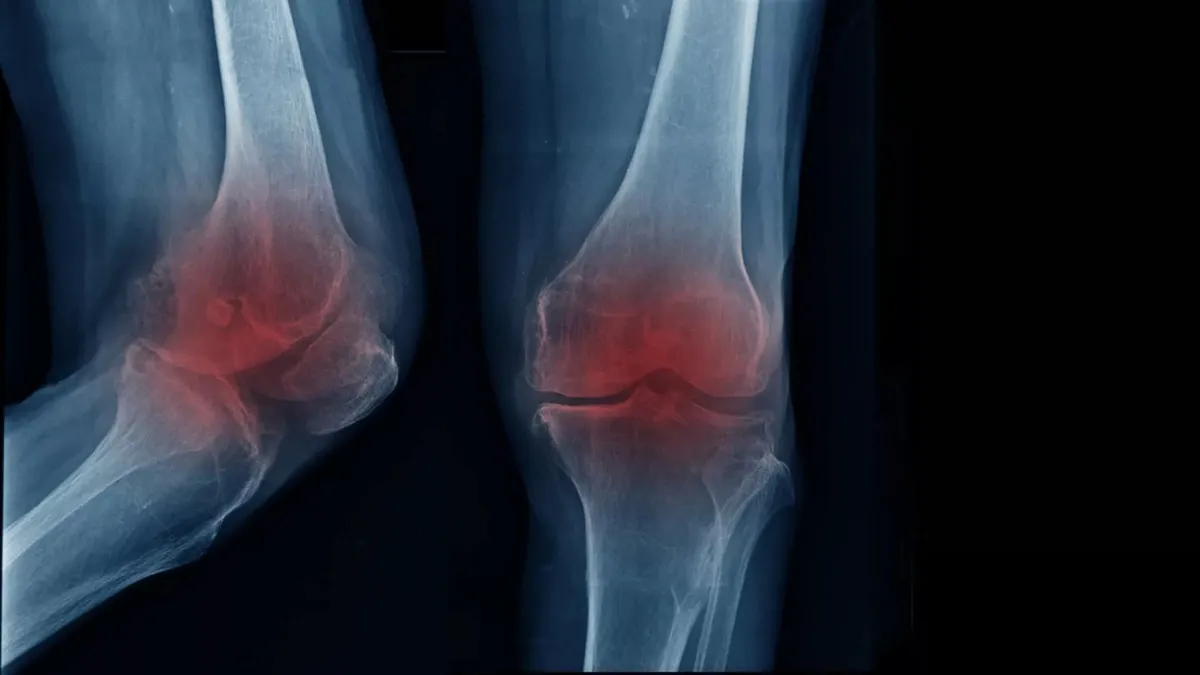

چطور آرتروز زانو با تقویت توده عضلانی قابل درمان است

اعضای این تیم دریافتند افرادی که در جریان انجام فعالیتهای ورزشی، زانوهایشان باید وزن بدن را تحمل کنند، در صورت داشتن سطح پایینی از توده عضلانی در اندام تحتانی، بیشتر از دیگران در معرض ابتلا به آرتروز زانو قرار دارند.

از آنجایی که تودههای عضلانی قویتر میتوانند از زانو در برابر فشارهای مکانیکی که به مفصلها وارد میشوند محافظت کنند، محققان انتظار داشتند که عضلات قویتر بهتر از عضلات ضعیفتر عمل کنند.